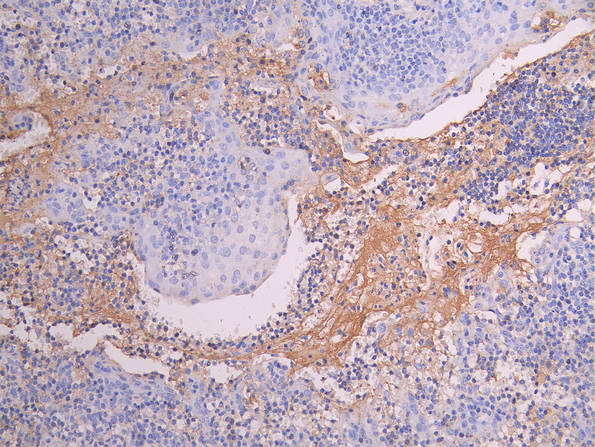

CSB-RA014679MA1HU

Tested Applications:

ELISA, IHC

CSB-RA240597A0HU

ELISA, WB, IHC